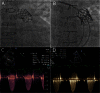

There is a growing appreciation for the adverse long-term impact of right-sided valvular dysfunction in patients with congenital heart disease. Although right-sided valvular stenosis and/or regurgitation is often better tolerated than left-sided valvular dysfunction in the short and intermediate term, the long-term consequences are numerous and include, but are not limited to, arrhythmias, heart failure, and multi-organ dysfunction. Surgical right-sided valve interventions have been performed for many decades, but the comorbidities associated with multiple surgeries are a concern. Transcatheter right-sided valve replacement is safe and effective and is being performed at an increasing number of centers around the world. It offers an alternative to traditional surgical techniques and may potentially alter the decision making process whereby valvular replacement is performed prior to the development of long-term sequelae of right-sided valvular dysfunction.